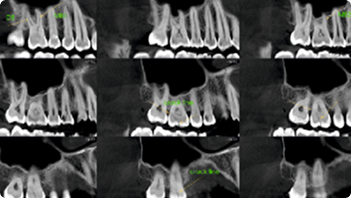

Endodontic Assessment

Periodontal Assessment